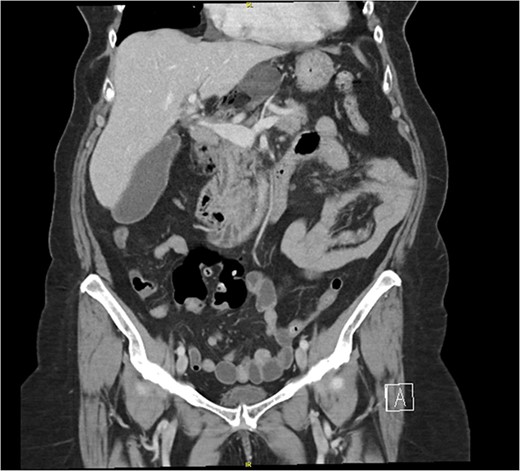

The patient’s laboratory values were significant for WBC 12.2 × 109/L, potassium 3.1 mmol/L, creatinine 0.59 mg/dl, lipase 676 U/L, total bilirubin 1.8 mg/dl, direct bilirubin of 0.6 mg/dL, ALT/AST 147/221 U/L, and alkaline phosphatase of 579 U/L. A computed tomography (CT) scan of the abdomen and pelvis with intravenous contrast demonstrated the cecum herniating through the foramen of Winslow with no signs of ischemia or bowel obstruction (Fig. 1); the gallbladder was distended with pericholecystic stranding and surrounding portal triad inflammation (Fig. 2).

Two coronal images from a computed tomography (CT) scan of the abdomen and pelvis with intravenous contrast demonstrating the cecum herniating through the foramen of Winslow with no signs of ischemia or bowel obstruction.